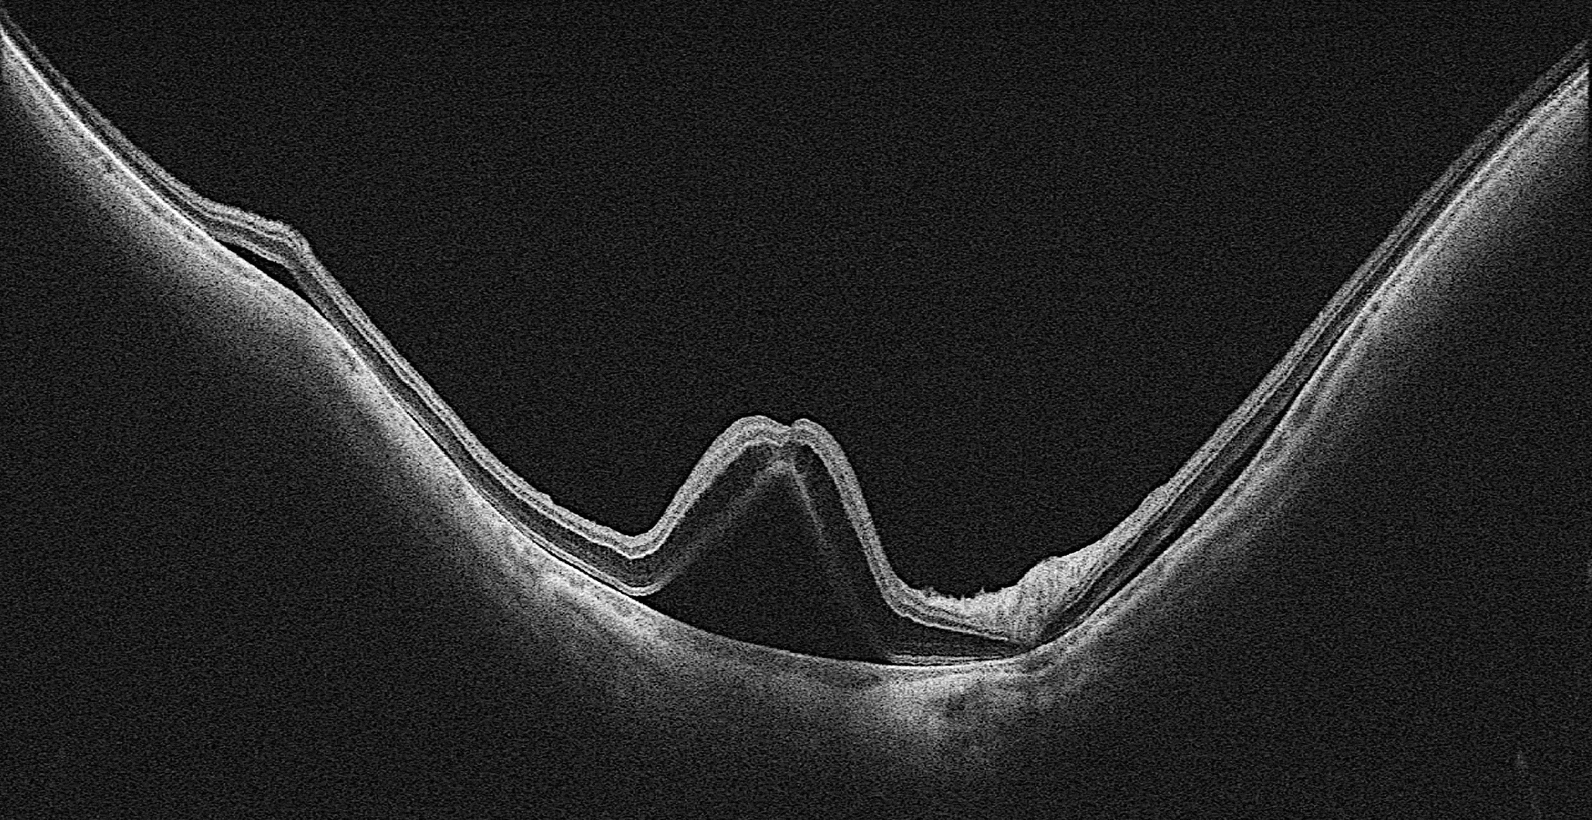

The UWF-OCT examination revealed that both the posterior pole and the mid-periphery of the retina were affected (Fig. 1). During the acute phase, we also detected SS-OCT hyperreflective foci in the vitreous chamber that were not visible on ultrasonography (Fig. 2). These foci partially persisted until 1 year after surgery. In two patients, the resolution of the macular serous retinal detachment led to visible structural OCT damage of the outer retina, which is likely to be permanent (Fig. 3). UWF-OCTA revealed an increase in SVD in the posterior pole and mid-periphery during the acute phase, while at the resolution of subretinal fluid, SVD decreased; it was only partially restored but did not return to preoperative values after 12 months. The deep vascular complex, choriocapillaris, and choroidal circulations did not appear to be damaged. Vascular involvement included not only the macular region but also the retinal mid-periphery (Fig. 4). Multifocal ERGs, after the loss observed at T1-T2, showed a gradual recovery of the foveal response amplitude at T3-T5 (Fig. 5).

Fig. 3

Spectral-domain optical coherence tomography of case 2 (left) and case 4 (right), showing images at the preoperative evaluation (top), the day after surgery (middle), and 1 week after surgery (bottom)

At T2, OCT showed the absence of retinal fluid, but a focal defect of the ellipsoid zone, not present at T0, was highlighted. The BCVA was 20/20, but the patient reported metamorphopsia. This condition persisted until the last follow-up at T3. OCTA demonstrated a gradual decrease in SVD at T2 and T3 compared to T1.

At T2, OCT showed the absence of retinal fluid but highlighted partial atrophy of the outer retina involving the foveal ellipsoid zone, which was not present at T0. The BCVA was 20/25. The differential light sensitivity improved compared to T1 but remained below the normative values. This condition persisted until the last follow-up at T3.